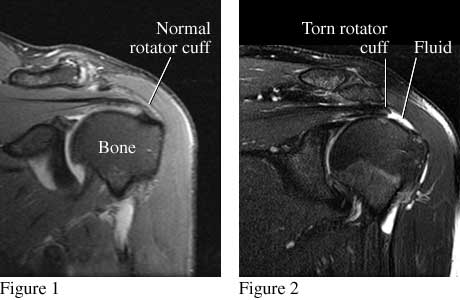

MRI images of torn rotator cuff

Courtesy of Intermountain Medical Imaging, Boise, Idaho. All rights reserved.

Figure 1 is a front view of the shoulder that shows a normal rotator cuff. Figure 2 is a similar view that shows a torn rotator cuff.